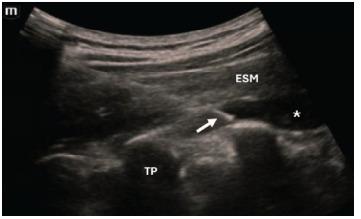

Breakthrough pain is frequently experienced by patients with gastrointestinal malignancies and is a common reason for presenting to the emergency department (ED). After ruling out acute pathology, ED management typically consists of intravenous opioids, although high doses of opioids can be associated with potentially severe adverse events and complications in certain high-risk populations. Regional anesthesia strategies, such as the erector spinae plane block (ESPB), have been shown to be effective for several etiologies of non-malignant visceral abdominal pain. In this case series we sought to evaluate whether the ESPB can be effective for ED patients with breakthrough pancreatic and hepatobiliary cancer pain.

Three patients with breakthrough hepatopancreatobiliary cancer pain underwent successful ESPBs performed by an emergency physician in the ED. All patients reported considerable reduction in their pain. Two patients with cancer of the pancreatic head reported complete pain relief and were able to be discharged from the ED. The third patient with metastatic colorectal cancer involving the hepatobiliary system was admitted for further medical workup, although he did not require any additional analgesics for nearly 13 hours after the block.